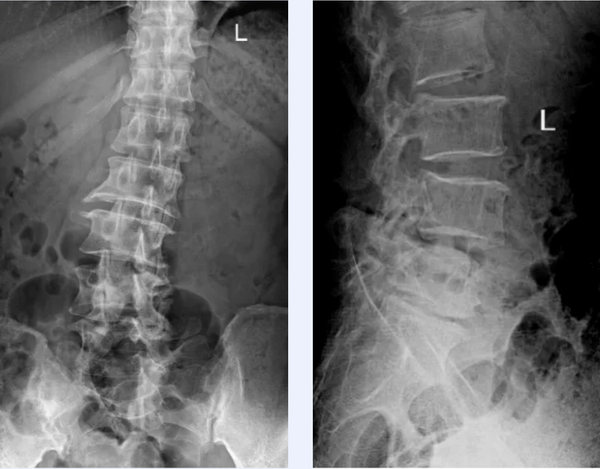

影像提示:腰椎退變滑脫、椎管重度狹窄,并椎體旋轉(zhuǎn)帶側(cè)凸

楊峻主任團(tuán)隊(duì)結(jié)合患者癥狀體征及影像檢查考慮患者為腰椎退變滑脫、重度椎管狹窄,脊髓神經(jīng)明顯受壓,導(dǎo)致腰骶和下肢疼麻及活動受限等病癥,需要予患者行椎管徹底減壓,解除脊髓神經(jīng)受壓,同時行融合內(nèi)固定。詳細(xì)閱讀相關(guān)影像結(jié)果,該患者腰椎增生退變及椎管狹窄較重,同時腰段椎體旋轉(zhuǎn)帶側(cè)凸,可導(dǎo)致術(shù)中解剖結(jié)構(gòu)辨識困難,脊髓神經(jīng)比鄰關(guān)系不清,手術(shù)難度大,風(fēng)險(xiǎn)高,手術(shù)復(fù)雜。為保證手術(shù)的安全性及精準(zhǔn)手術(shù)操作,防止損傷脊髓神經(jīng),降低手術(shù)風(fēng)險(xiǎn),楊峻主任團(tuán)隊(duì)決定借助最先進(jìn)的3D數(shù)字打印技術(shù)為其實(shí)施腰椎減壓融合內(nèi)固定術(shù)。